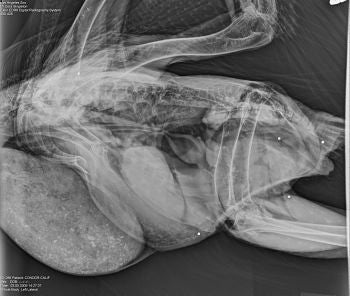

Condor #286, dubbed "Pinns" because he's one of the oldest condors released at Pinnacles National Monument, was rescued by Ventana Wildlife Society biologists. He'd been shot and was suffering from lead poisoning. Courtesy Ventana Wildlife Society.

As for the two wounded condors, they are recuperating at the Los Angeles Zoo. The male, #286, is in critical condition after being hit with 15 buckshot pellets (see photos below - courtesy Ventana Wildlife Society); his digestive system is debilitated due to lead poisoning and veterinarians must feed him through a tube. The second condor, #375, is in better condition, but the pellet injured her left wing and it’s unclear whether she will be able to fly; she was hit by a total of three pellets.